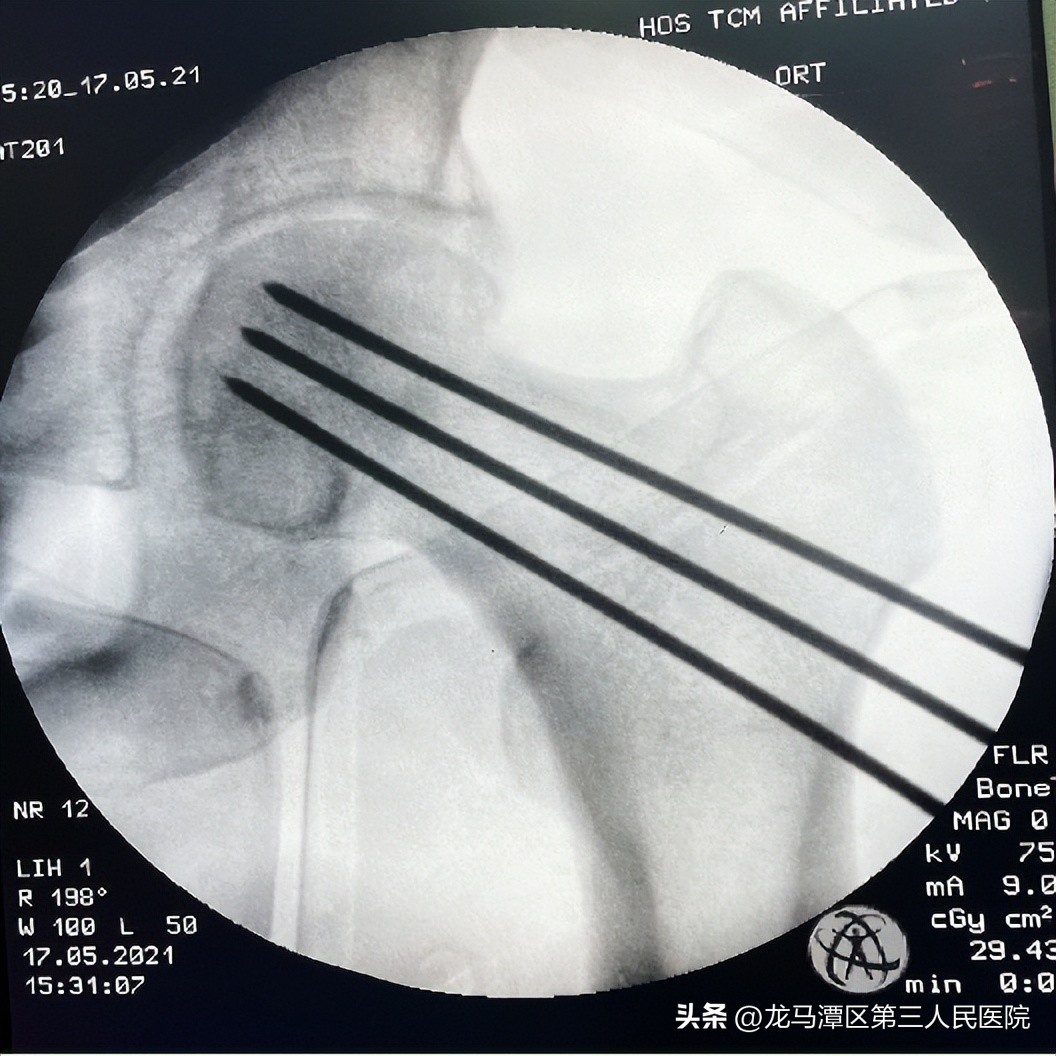

转孔减压--三角形支撑

提供新的毛细血管爬行通道,改变塌陷及骨髓水肿,缓解骨内压力,增强坏死骨的爬行代替,形成稳定的三角形支撑。钻孔减压抽吸治疗采用椎体成形工具,降低骨内高压、解除骨内瘀,改善股骨头血供,修复创造条件。髋关节镜联合钻孔减压术并不是2种技术的简单叠加,关节镜术中对于关节腔股骨头软骨、滑膜、圆韧带、盂唇、关节周围疼痛的观察与处理,手术效果好,提高复合治疗的应用。